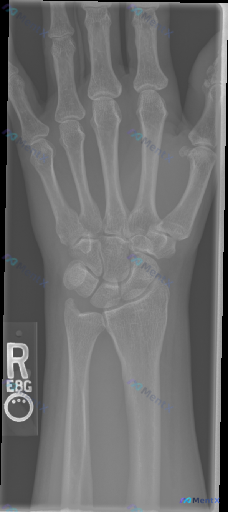

这张右手腕X光片的异常,你第一时间会抓住什么?

影像观察到的关键信息:

- 骨骼完整性:桡骨远端、腕骨序列、掌骨及指骨未见明确皮质断裂;但在尺骨茎突部位可见明显的皮质不连续,有一条透亮的骨折线,骨折块有轻微分离移位。

- 关节间隙与对合:桡腕关节、腕中关节及腕掌关节间隙清晰,腕骨排列基本正常,下尺桡关节对位尚可,未见明显脱位或半脱位。

- 骨结构与密度:整体骨密度未见明显异常,骨小梁清晰;尺骨茎突骨折区域周围的软组织影稍显增厚。

- 创伤背景提示:这类表现常见于腕关节外伤,影像上骨折线清晰、边缘锐利,无明显骨痂形成。